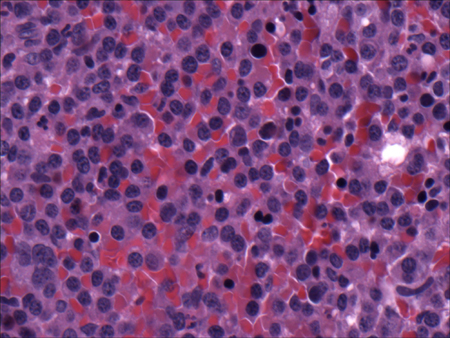

- biopsia renal:

los glomérulos tienen depósitos grandes semejantes a una joroba subepitelial; las semilunas celulares y la proliferación endocapilar son frecuentes y los glomérulos pueden tener una apariencia membranoproliferativa